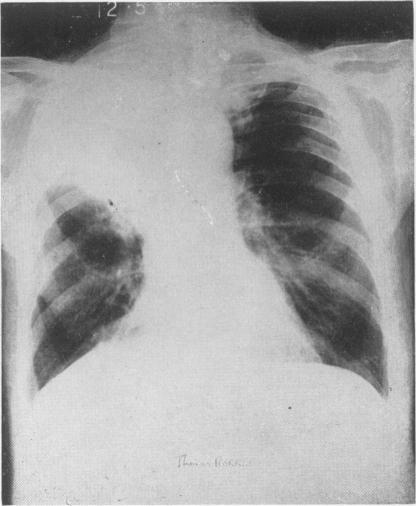

Co-existent pulmonary tuberculosis and bronchogenic carcinoma.

Postgrad Med J. 1956 Apr;32(366):213-5. doi: 10.1136/pgmj.32.366.213.